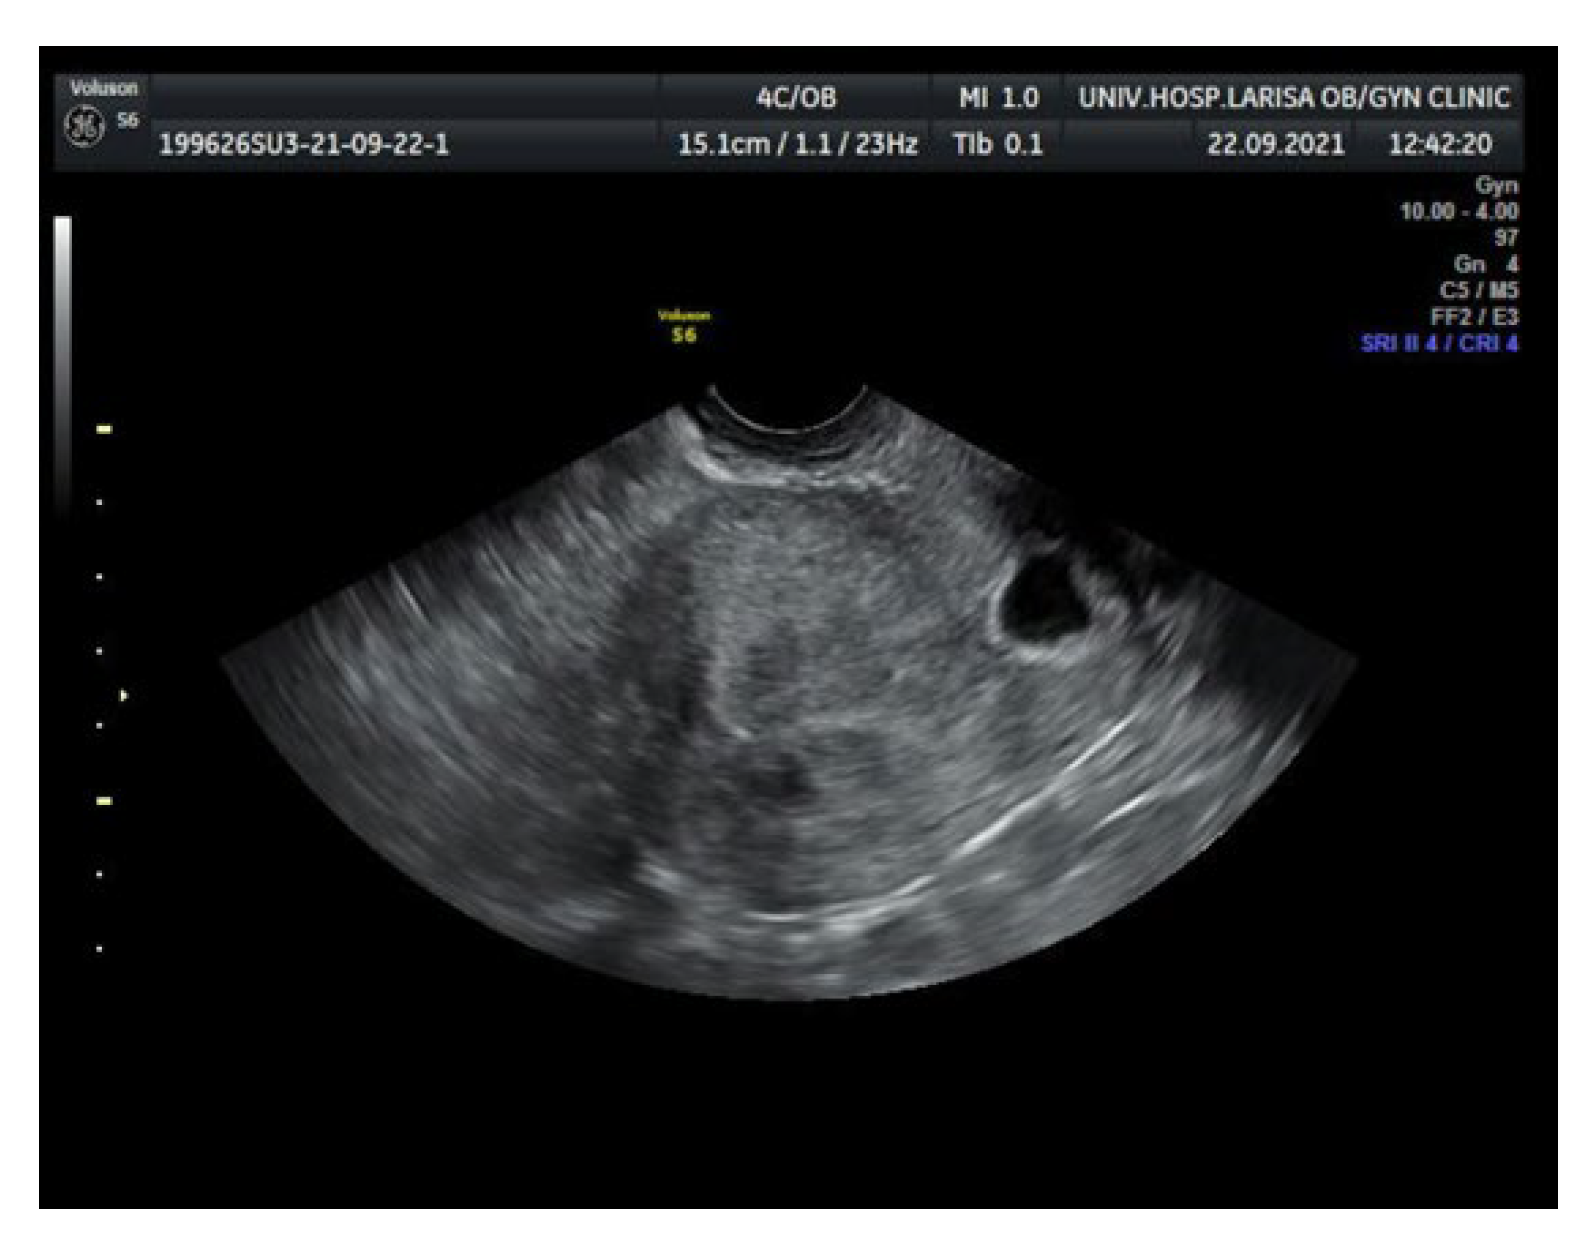

2. Case Report

| Empty endometrial and endocervical cavity |

| Nested gestational sac and placenta on/in the scar |

| Triangular (≤8/40 weeks) rounded or oval shaped gestational sac (≥8/40 weeks) filling the scar “niche” |

| Thin (1–3 mm) or absent layer of myometrium between the urinary bladder and the gestational sac |

| Distinct or rich vascular pattern around the area of the scar |

| Embryonic or fetal pole, yolk sac, or both with presence or absence of fetal cardiac activity |